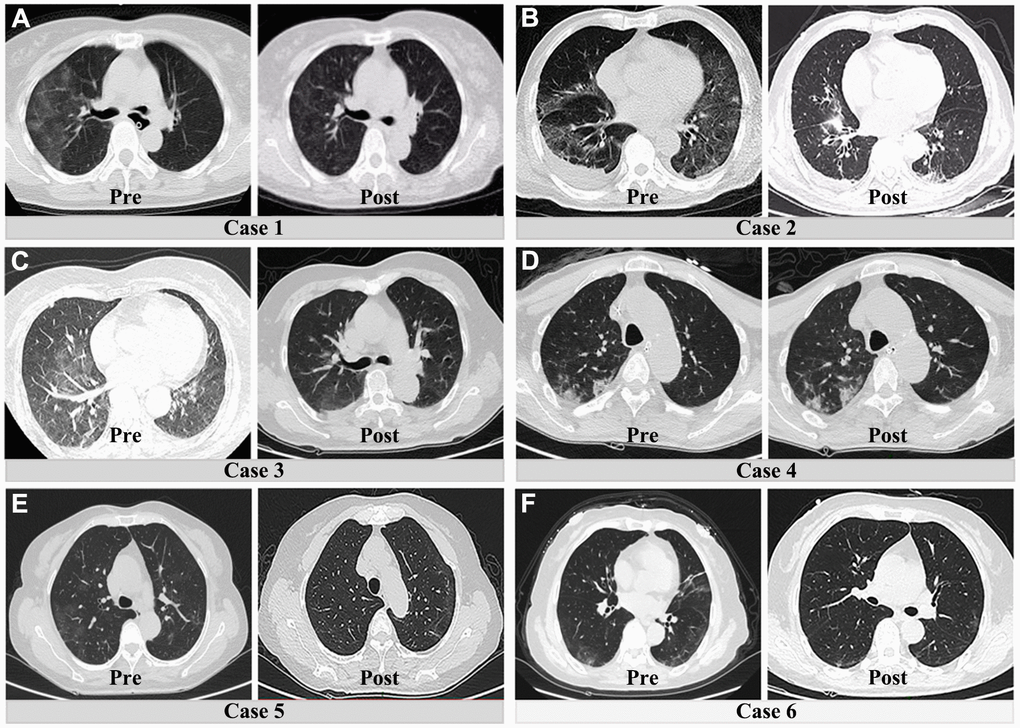

To remove the potential impact of age on the above results, we further compared the pre- and postsurgical differences between patients with COVID-19 and those without COVID-19 pneumonia (between 60 and 80 years old). After age-matching between both groups, the majority of preoperative and postoperative results were consistent with the previous results. As shown in Table 3, patients with COVID-19 pneumonia still had poor preoperative liver and coagulation function. However, the bulk of abnormal preoperative laboratory findings were significantly and rapidly corrected after surgical treatment (Figure 4). In addition, an obvious resolution of lung inflammation was observed after surgery in five patients (83.3%) (Figure 5). These results indicated that COVID-19 pneumonia is associated with poor liver function and coagulation function in acute abdomen patients with COVID-19 pneumonia. Nevertheless, emergency surgery could not only improve the outcomes of COVID-19 pneumonia patients with acute abdomen, but also benefit the resolution of pulmonary inflammation.

Figure 5. Preoperative and postoperative CT lung manifestations in six patients with both acute abdomen and COVID-19 pneumonia. (A–C) and (E, F) show the obvious resolution of pulmonary inflammation. The fourth patient had no significant change of pulmonary inflammation after surgical treatment (D).